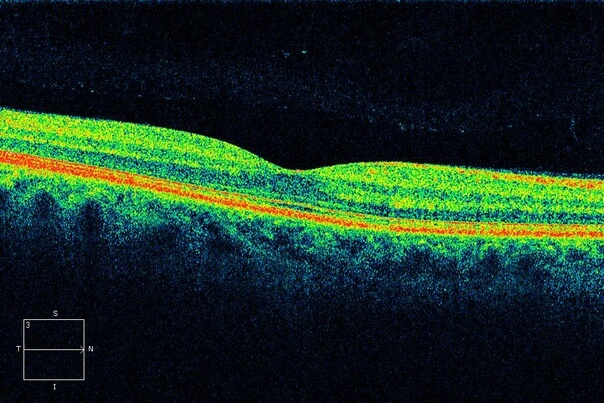

Именно оптическая когерентная томография позволяет получать наиболее качественные изображения сетчатки глаза, распознавая мельчайшие и самые ранние изменения, сопровождающие макулярную дегенерацию.

Оптическая когерентная томография (ОКТ) сканирует отдельные слои сетчатки, что позволяет выявить изменения внутри ткани и определить форму дистрофии.

Если при обычном офтальмоскопическом исследовании обнаруживается несоответствие остроты зрения и картины глазного дна, ОКТ позволит определить окончательный диагноз. Также данное исследование незаменимо для контроля эффективности проводимого лечения.